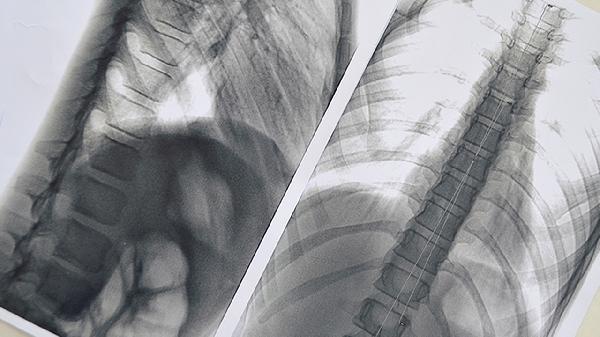

肺结节是否需干预主要取决于影像学特征和生长速度。8毫米实性结节若边缘光滑、无毛刺征或分叶征,随访1-2年无增大时多为良性病变,如肺内淋巴结或肉芽肿性改变。此类情况每6-12个月进行低剂量CT复查即可,无须特殊治疗。但需注意戒烟并避免二手烟暴露,减少呼吸道刺激因素。对于存在慢性咳嗽或痰中带血等伴随症状者,可配合支气管舒张剂或祛痰药物缓解症状。

当结节呈现磨玻璃成分、短毛刺、胸膜牵拉等恶性征象,或随访中发现体积增大20%以上时,需考虑手术切除。胸腔镜下肺段切除术是常用术式,术后病理可明确诊断。高龄或手术高风险患者可选择CT引导下穿刺活检,明确性质后制定个体化方案。合并咯血、消瘦等全身症状者应完善肿瘤标志物和全身评估,排除转移可能。